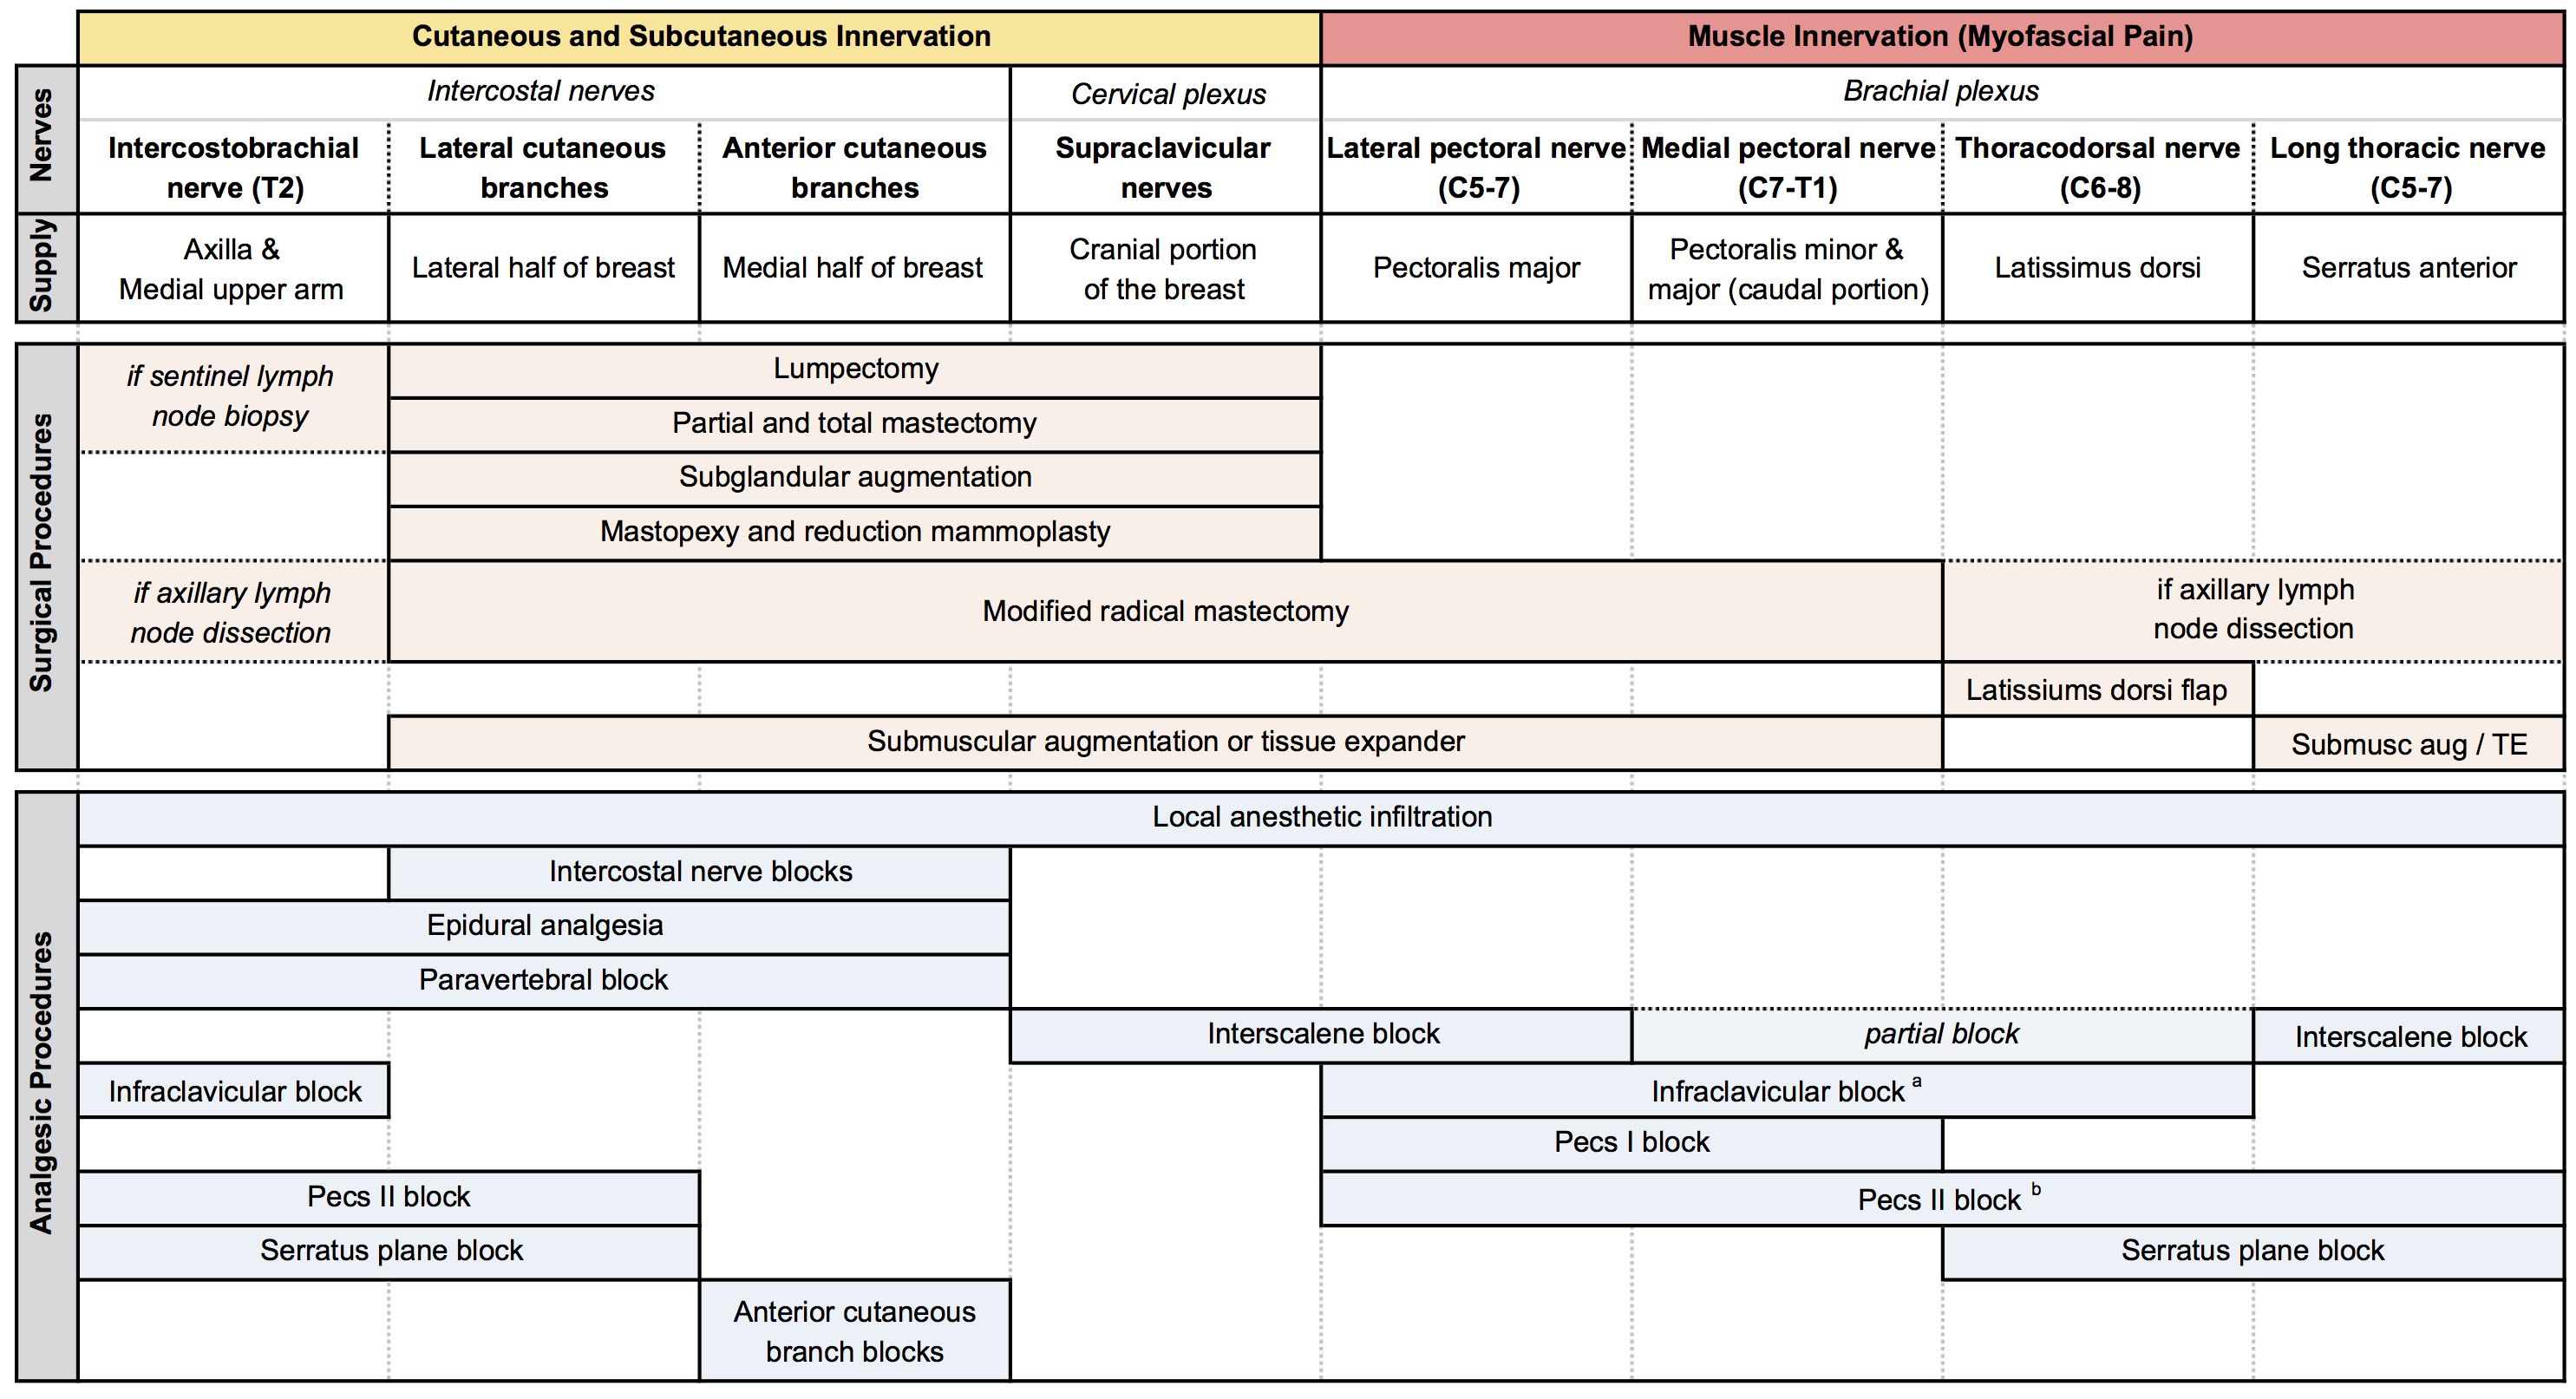

Breast cancer is the most commonly diagnosed cancer in women, and standard surgical therapy has undergone a number of substantial changes in recent years. The once-popular radical mastectomy is now rarely used. Newer techniques include the modified radical mastectomy, simple mastectomy, and sentinel lymph node biopsy (SLNB), described in Table 1.[1] When considering regional anesthetic (RA) techniques for breast surgery, physicians must have a significant understanding of the types of breast surgery, correlating innervation, and RA technique efficacy (Table 2) to tailor a patient-specific analgesic and anesthetic plan.

A variety of RA techniques may provide effective analgesia for breast surgery. The options highlighted in Figure 2 and Table 2 include paravertebral blockade (PVB), erector spinae plane block (ESPB), and pectoral nerve block (PECS II). Epidural analgesia and serratus plane blocks are additional techniques for effective breast analgesia.

Table 3: Summary of chest wall innervation, breast surgeries, and analgesic procedures.[2] (Click to enlarge image.)

PECS blocks are becoming an increasingly popular technique for the provision of breast analgesia. PECS I blocks the medial and lateral pectoral nerves, which are situated in between the pectoralis minor and major muscles on the anterolateral chest. PECS II includes the PECS I block and an injection of local anesthetic into a plane more lateral on the chest wall and between the pectoralis minor and serratus anterior muscles, targeting the lateral cutaneous branches of the intercostal nerves, long thoracic nerve, and thoracodorsal nerve (Figure 5).[2] PECS II has been shown to be associated with lower postoperative pain scores and opioid consumption similar to PVB. However, the data is currently limited in terms of confirming which block is superior and they can both provide surgical anesthesia. The PECS block may be better tolerated by patients and easier to perform in the setting of decreased ancillary support or in an anesthetized patient. More extensive surgeries may require additional blocks to provide coverage for axillary procedures or medial breast analgesia.[6]

The serratus plane block is another useful adjunct for chest surgery and is performed more lateral and caudad than the PECS II at the fifth rib in the midaxillary line. Local anesthetic is deposited between the serratus anterior and the latissimus dorsi muscles, with the thoracodorsal artery being an indicator of the plane’s location, to provide a sensory block to the T2–T9 dermatomes via extended intercostal nerve coverage. Local anesthetic can also be deposited in the plane deep to the serratus anterior muscle with similar analgesic efficacy. A PECS I block is required to provide analgesia to pectoral muscles, and, similar to a PECS II block, medial breast incisions will require local anesthetic supplementation.[2]